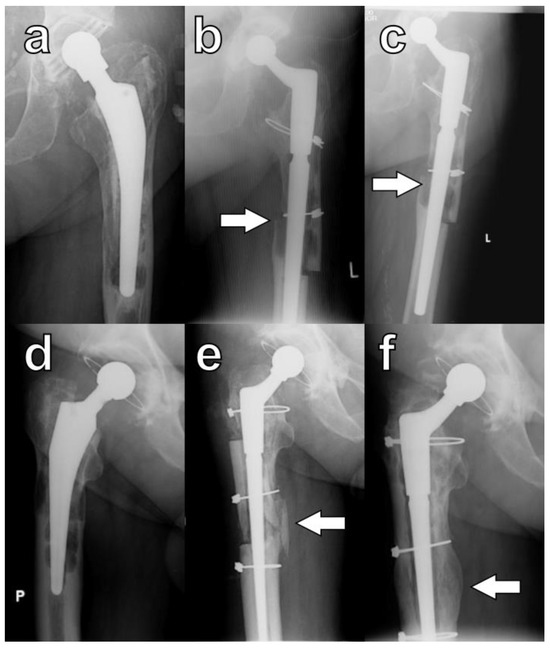

In this study, during the final evaluation, a lack of osteotomy union on any of the orthogonal radiographs was observed in four hips (9.5%). However, this phenomenon was not associated with decreased functional outcomes, and none of these patients required revision procedures (Figure 5a–c). In five hips, despite careful surgical techniques, large cortical bone fragments denuded of muscle were inadvertently broken off intraoperatively. Each of these devascularized fragments was subsequently attached to the femoral stem, and in all cases, osseointegration was observed (Figure 5d–f).

Figure 5.

Specific cases of ETO healing: lack of bone formation within the osteotomy (a) pre-op, (b) at six months, and (c) at twenty-four months. Osseointegration of a devascularized bone fragment: (d) pre-op, (e) at three months, and (f) at six months; arrows indicate osteotomy sites. P is right side, and L is left side.